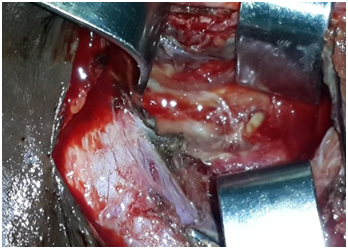

Case 2: A 24-year-old man complaining of torticollis, and dysphagia, evolving for 6 days. The patient reported ingestion of fish bone. The clinical examination founded, hypersialorrhea, a painful cervical node. X ray showed the foreign body (Figure 3). The extraction of the fish bone (Figure 4), the drainage of abscess and the trimming of the oesophageal wound were done by external surgical approach. During the extraction the carotid was notched. One month later, clinical and radiological examination were normal.

Figure 4 Fish bone.

Figure 5 During cervicotomy carotid was notched (flèche).